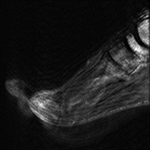

Motion Artifact. Degraded image quality of sagittal T1-weighted fat-saturated post-contrast MR image of the foot due to patient motion.